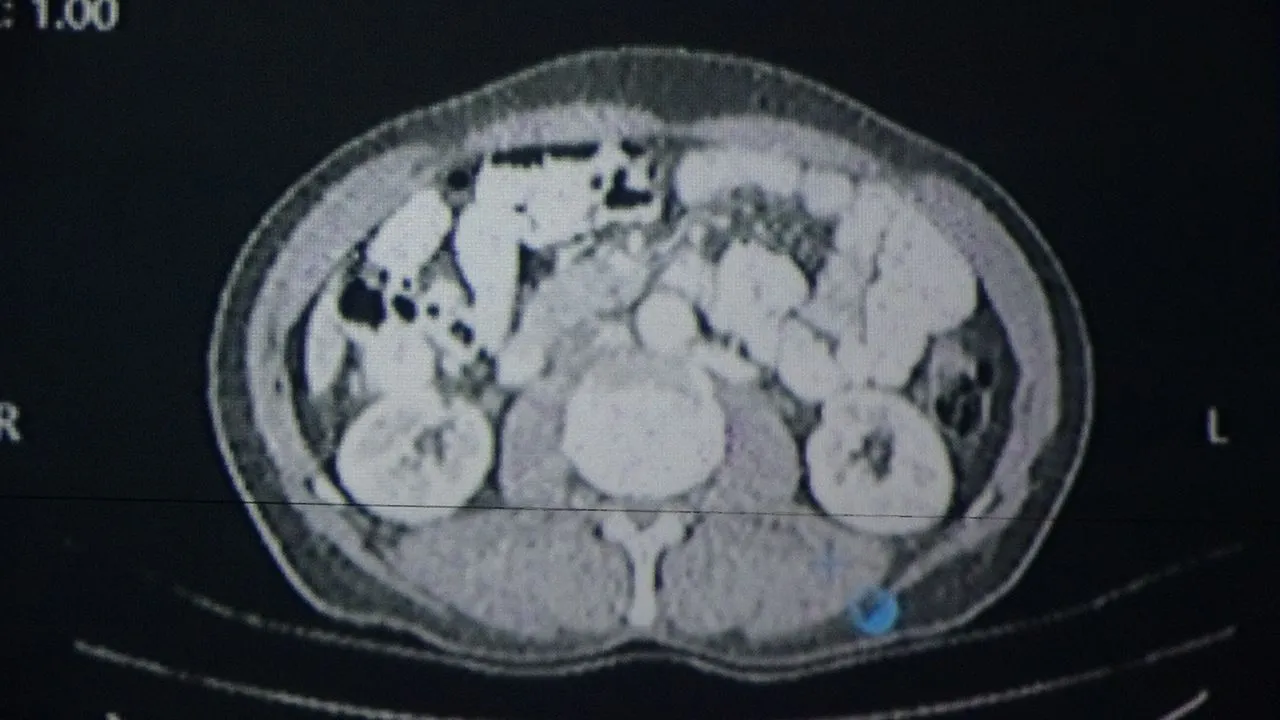

Konuya ilişkin konuşan Van Bölge Eğitim ve Araştırma Hastanesi Genel Cerrahi Uzmanı Prof. Dr. Sebahattin Çelik, yapay zekânın hekim kararlarıyla yüzde 76 oranında örtüştüğünü belirtti. Yapay zekânın sağlık alanında giderek daha yaygın kullanıldığı ifade eden Prof. Dr. Çelik, "Biz de Van Bölge Eğitim ve Araştırma Hastanesi olarak teknolojinin sunduğu en son imkânlardan faydalanarak hastalarımıza doğru tedaviyi ve doğru yaklaşımı sunmak için yapay zekâ algoritmalarını kullanıyoruz. Yakın zamanda prestijli bir dergide yayımlanan çalışmamızda, multidisipliner tümör konseylerinde yapay zekâ destekli bir yazılım kullandık. Bu konseylerde genel cerrahi, onkoloji, radyoloji, nükleer tıp, radyasyon onkolojisi ve patoloji gibi birçok farklı branştan uzman hekimler bir araya gelerek hastaların tedavi sürecine yönelik ortak kararlar almaktadır. Biz de bu konsey toplantılarında yapay zekâyı bir katılımcı olarak değerlendirdik. ChatGPT'nin son algoritmasını kullanarak kanser tanısı olan 100 hastamızı hem uzman hekimler hem de yapay zekâ değerlendirdi. Sonrasında alınan kararlar karşılaştırıldığında, yapay zekâ destekli verilen kararların hekimlerin kararlarıyla yaklaşık yüzde 76 oranında örtüştüğünü gördük. Bu oldukça çarpıcı ve önemli bir bulgudur. Çünkü bu durum, yapay zekâ algoritmalarının artık profesyonel bir meslek grubu olan doktorlara yakın düzeyde karar verebildiğini göstermektedir" dedi.